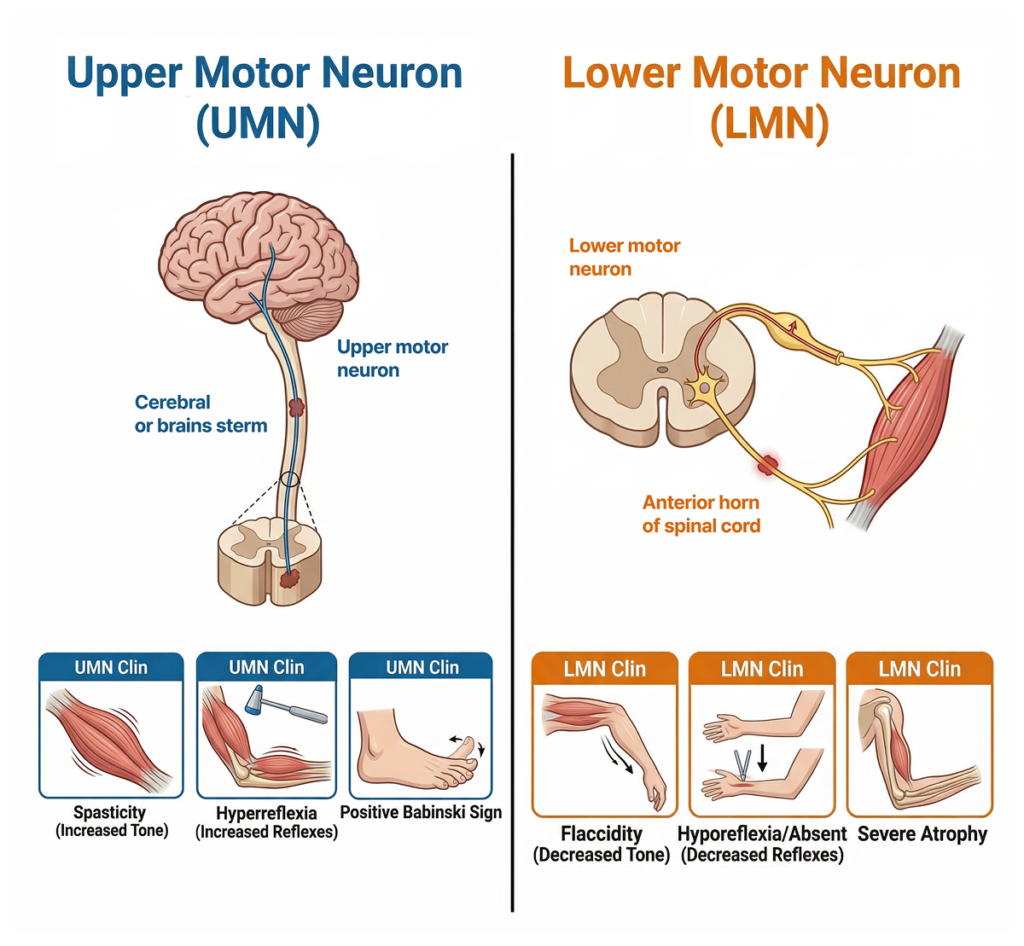

2. ALS의 핵심 : UMN + LMN이 동시에 무너진다

ALS를 이해하는 가장 중요한 포인트는 이것 하나입니다.

👉 상위운동신경원 (Upper Motor Neuron) + 하위운동신경원 (Lower Motor Neuron) 이 동시 침범

이게 왜 중요할까요?

UMN 손상

- 경직

- 반사항진

- 바빈스키 징후 (+)

LMN 손상

- 근위축

- 근육떨림

- 근긴장 감소

대부분의 질환은 한쪽 축만 무너집니다.

👉 그런데 ALS는 두 축이 동시에 무너집니다.